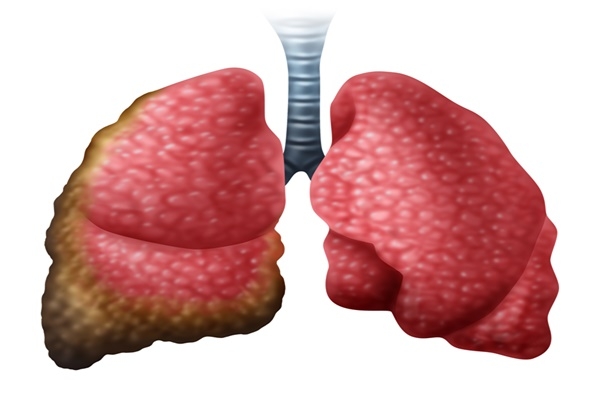

폐렴 증상 3. 호흡 곤란 및 숨 가쁨

폐에 염증이 생기면 산소 교환이 어려워져

숨이 차고 가슴이 조이는 느낌,

또는 평소보다 가쁜 숨, 짧은 호흡이 나타날 수 있어요.

계단을 오르거나 평소보다 조금만 움직여도 숨이 찰 수 있습니다.4. 흉통(가슴 통증)